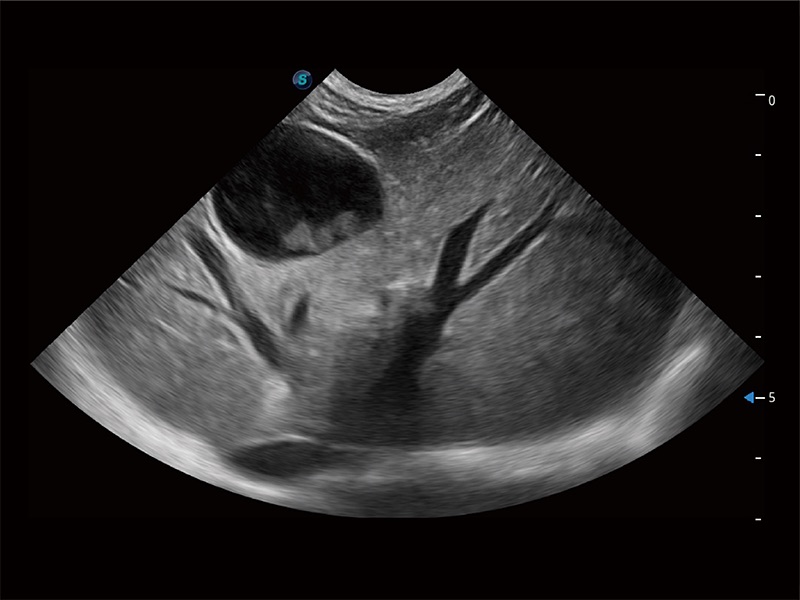

高性能和先进的临床应用工具可以为动物医生提供临床信心。ProPet 80 搭载了先进的腹部和浅表应用工具,帮助医生在日常临床实践中发挥前所未有的作用。

ProPet 80 专为动物医生设计,对不同的动物体型和生理结构作出了针对性的优化。通过动物影像专用软件,可满足个性化的应用需求,帮助动物医生获得更精确的诊断数据。

为精细结构及组织边缘提供高清晰度的图像和更大的成像视野。帮助减轻医生的用眼疲劳,快速精准获得测量的数据。